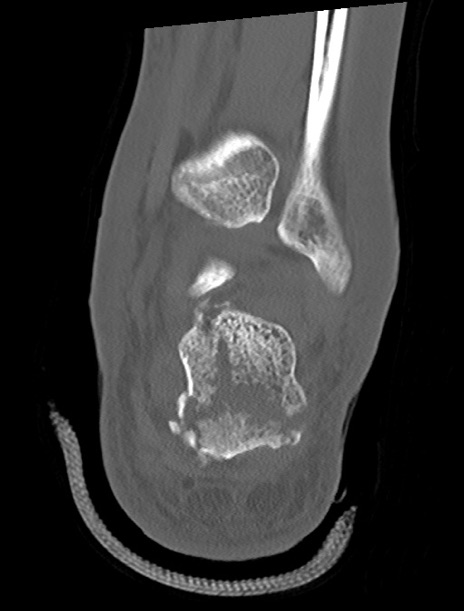

症例37 左足関節CT(冠状断像)

左足関節CT

矢状断像